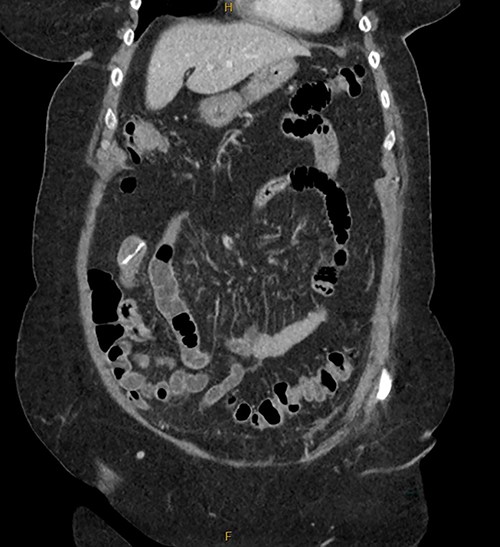

The acute surgical unit consulted upon the patient and a CT abdomen with oral contrast was performed the next day. CT was unable to accurately identify the position and nature of the foreign object. Filling defects with the stomach fundus and superior part of duodenum were identified, but the FB remained unidentified.

A magnetic cholangiopancreatography (MRCP) was performed to exclude a cholecystoduodenal fistula. A filling defect within the duodenum was identified on the scan; however, there was no evidence of a fistula (Fig. 6).

Secondly, as shown in the three cases, unless the BC is calcified, abdominal plain films are not a reliable method of tracking nor diagnosing BC ingestion [9–13]. CT is more sensitive, with a sensitivity rate of 67%, but is not consistently reliable on its own [6, 7]. Reconstructed 3D imaging is effective in identifying BCs. Most BCs are made of low-density polystyrene, a type of versatile solid plastic, which are not readily identified on plain film imaging [14, 15]. This non-degradable plastic means that it is usually only a matter of time before a patient develops a complication.